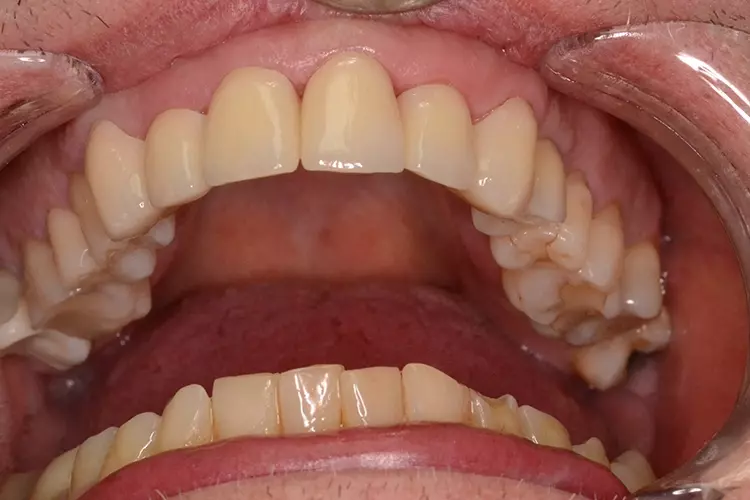

Bei dem heute 49-jährigen Patienten wurde seit Kindertagen versäumt, die Ober- und Unterkieferzahnbögen kieferorthopädisch auszurichten. Der Patient leidet seitdem stark unter seinen Zahnfehlstellungen.

Die Fraktur des stark elongierten Zahnes 21 war für den Patienten der Ausgangspunkt, sowohl die Front des Ober- als auch des Unterkiefers prothetisch überarbeiten zu lassen. Dabei wurde der frakturierte Zahn 21 durch ein navigiert eingesetztes Sofortimplantat ersetzt, während die verschachtelt stehenden Zähne 12 und 42 durch eine Brückenversorgung korrigiert wurden (Abb. 4a-j).